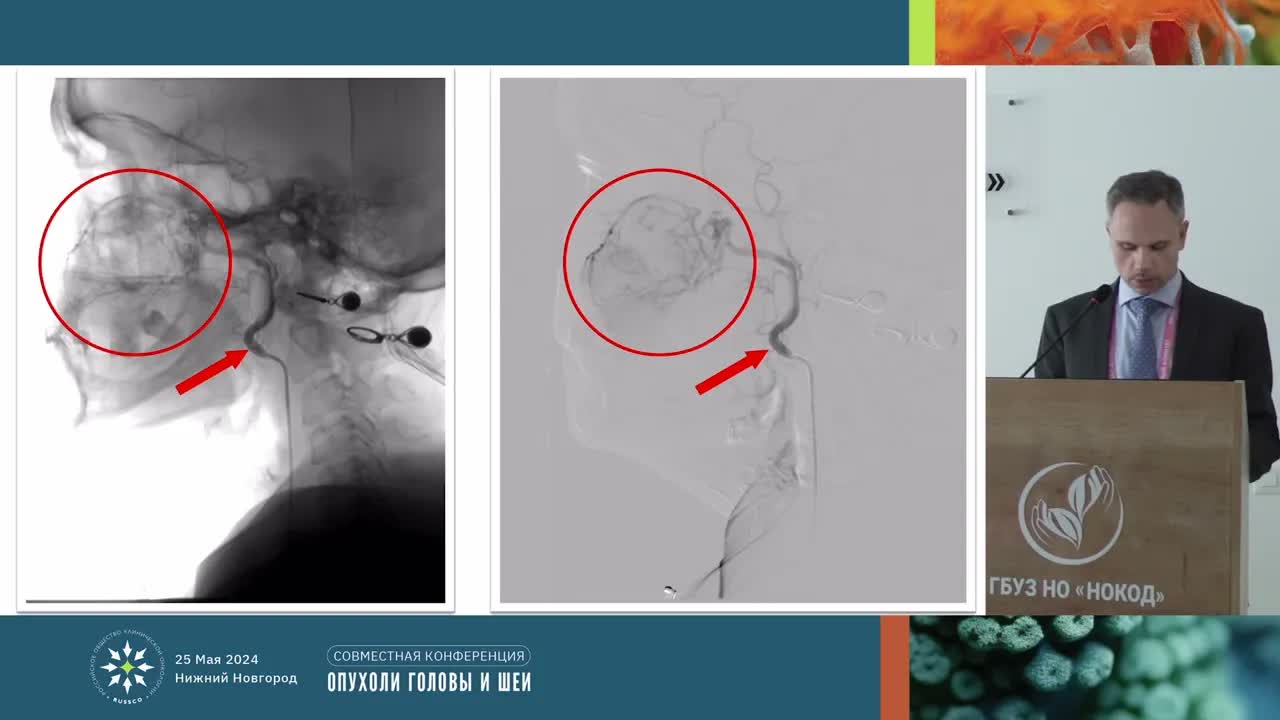

Результаты внутриартериальной химиотерапии местнораспространенных опухолей головы и шеи. Опыт НОКОД

Дерябин Роман Александрович